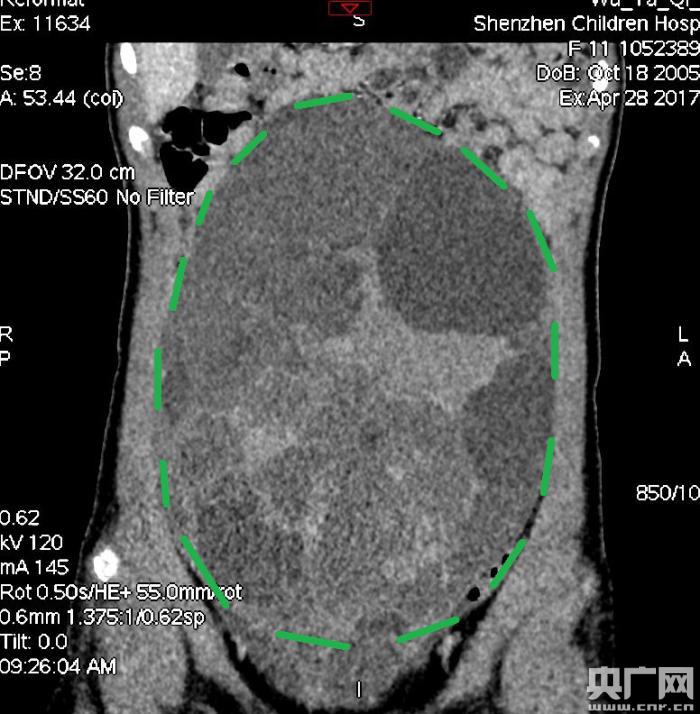

入院后,普外一科肖東主任向家長(zhǎng)詢問(wèn)了病史,仔細(xì)進(jìn)行了體格檢查,并完善腹部CT。CT結(jié)果提示,孩子的大部分腹腔、盆腔被一個(gè)巨大的腫瘤占據(jù),腸道、血管和腎盂都受到了不同程度的壓迫。從CT上看,腫瘤很可能起源于左側(cè)的卵巢。

手術(shù)中發(fā)現(xiàn),小琪腹中的腫瘤體積巨大,大小約為25×20×15厘米,表面光滑,來(lái)源于左側(cè)卵巢。醫(yī)生們首先將其與周圍的組織小心剝離,然后將這個(gè)占據(jù)孩子腹腔、盆腔大部分的巨大包塊完整切除,切除腫瘤后還重建了左側(cè)卵巢。剖開(kāi)瘤體,發(fā)現(xiàn)瘤體為囊性及實(shí)性混合組成,瘤體內(nèi)部充盈著粘液狀的液體,重量達(dá)到了3000克。術(shù)后小琪病情穩(wěn)定,測(cè)量腹圍從術(shù)前的72厘米減小到了62厘米。